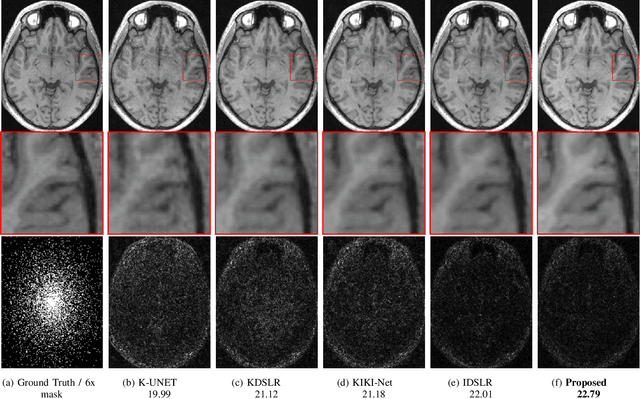

Abstract:We introduce a fast model based deep learning approach for calibrationless parallel MRI reconstruction. The proposed scheme is a non-linear generalization of structured low rank (SLR) methods that self learn linear annihilation filters from the same subject. It pre-learns non-linear annihilation relations in the Fourier domain from exemplar data. The pre-learning strategy significantly reduces the computational complexity, making the proposed scheme three orders of magnitude faster than SLR schemes. The proposed framework also allows the use of a complementary spatial domain prior; the hybrid regularization scheme offers improved performance over calibrated image domain MoDL approach. The calibrationless strategy minimizes potential mismatches between calibration data and the main scan, while eliminating the need for a fully sampled calibration region.

Abstract:Structured low-rank (SLR) algorithms are emerging as powerful image reconstruction approaches because they can capitalize on several signal properties, which conventional image-based approaches have difficulty in exploiting. The main challenge with this scheme that self learns an annihilation convolutional filterbank from the undersampled data is its high computational complexity. We introduce a deep-learning approach to quite significantly reduce the computational complexity of SLR schemes. Specifically, we pre-learn a CNN-based annihilation filterbank from exemplar data, which is used as a prior in a model-based reconstruction scheme. The CNN parameters are learned in an end-to-end fashion by un-rolling the iterative algorithm. The main difference of the proposed scheme with current model-based deep learning strategies is the learning of non-linear annihilation relations in Fourier space using a modelbased framework. The experimental comparisons show that the proposed scheme can offer similar performance as SLR schemes in the calibrationless parallel MRI setting, while reducing the run-time by around three orders of magnitude. We also combine the proposed scheme with image domain priors, which are complementary, thus further improving the performance over SLR schemes.